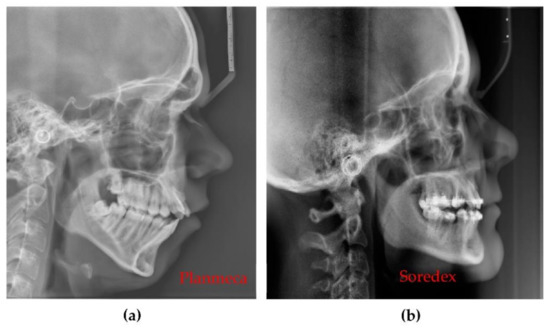

3.4. Differences Between the Planmeca and the Soredex System

| Panoramic | Planmeca and Soredex | Radiation dose is almost 50% smaller for Planmeca. Resolution is lower (127 µm) for Planmeca than for Soredex (100 µm). Images produced by Soredex have a lower contrast and sharpness even if they have better resolutions. |

| 3D CBCT | Planmeca and Soredex | Smaller exposure time (5 versus 9 s), smaller radiation dose (with at least 10 µSv), and smaller voxel side (with 25%) for Planmeca, which means better resolution, contrast, and image quality. The covered volume is larger for Soredex. |